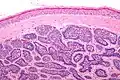

Dermal cylindroma. Puzzle-like distribution of tumour foci.